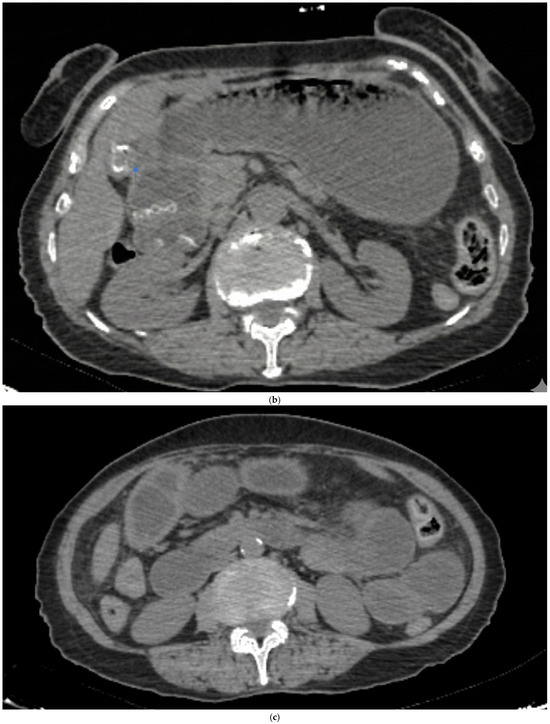

Embryo Sign on Abdominal CT as the Footprint of Cecal Volvulus: Improved Practice Through Lessons Learned from a Case Report

Cecal volvulus is a rare cause of acute abdominal pain, resulting from torsion of the cecum and ascending colon due to abnormal mobility caused by inadequate peritoneal fixation. Clinical presentation is often vague and nonspecific, which can delay diagnosis and treatment. Computed tomography [...] Read more.

Cecal volvulus is a rare cause of acute abdominal pain, resulting from torsion of the cecum and ascending colon due to abnormal mobility caused by inadequate peritoneal fixation. Clinical presentation is often vague and nonspecific, which can delay diagnosis and treatment. Computed tomography (CT) is the imaging modality of choice, as it not only confirms the presence and location of the volvulus but also identifies serious complications such as ischemia or perforation. Abdominal radiographs may be inconclusive, especially when the twisted bowel loop is fluid-filled, aligned antero-posteriorly, or obscured by adjacent gas-filled loops. We present the case of a 65-year-old woman who arrived at the emergency department with sudden-onset abdominal pain. Abdominal CT revealed classic signs of cecal volvulus, including the rarely reported ‘embryo sign,’ which proved crucial for swift diagnosis and intervention. Recognizing both common and less common CT features, such as the embryo sign, is paramount for rapid diagnosis and appropriate management in emergency situations. Familiarity with the full radiologic spectrum of this condition can significantly improve patient outcomes. Full article